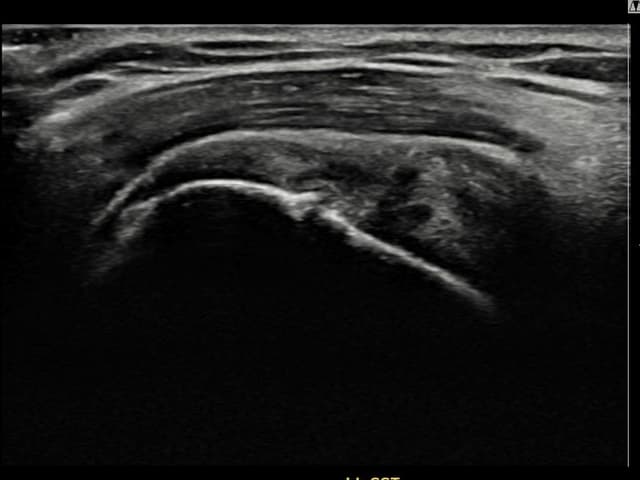

[経過期間: 23.08.16~23.10.18]

[縫縮術] 超音波検査にて右 棘上筋腱 関節面側部分断裂(7mm × 3mm (腱厚の約30%欠損))を確認。縫縮術施行後、腱の連続性が回復し、日常生活に復帰されました。